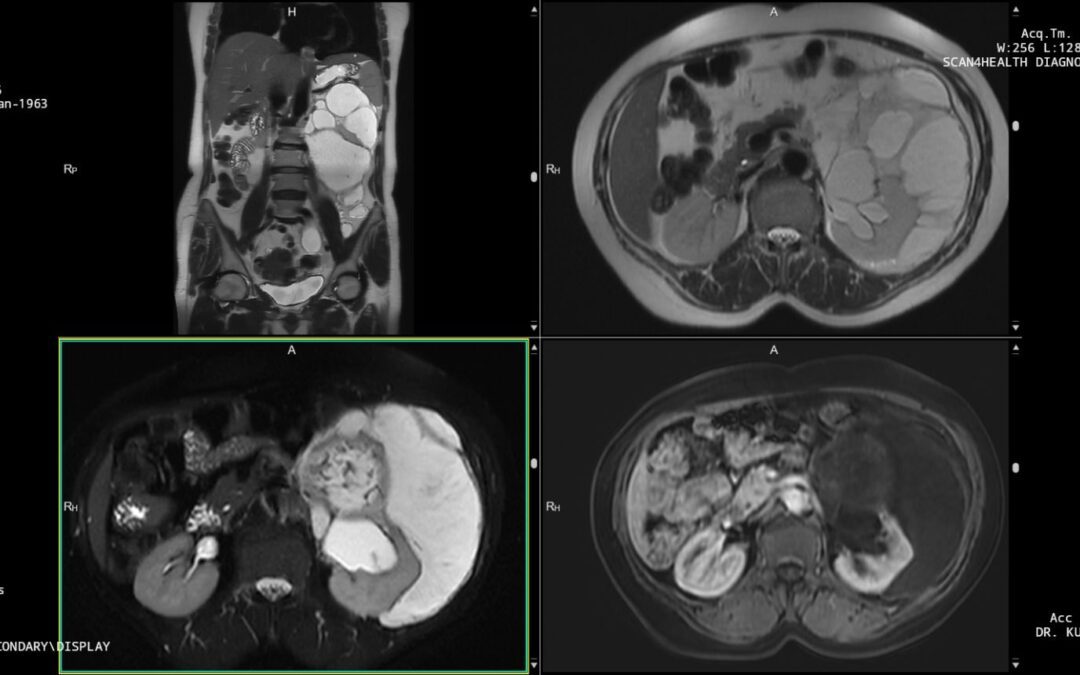

MRI KUB Retroperitoneal Case: A 62-year-old female presented with Persistent Left Flank Pain for two months. Initial clinical evaluation suggested a possible renal mass.A Digital Contrast-Enhanced MRI KUB was performed at Scan4Health, using high-resolution dynamic...